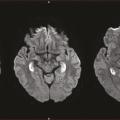

Les maladies de la mémoire peuvent être classées en deux groupes : celles qui donnent une amnésie transitoire, généralement très brève (voir le focus « Amnésies transitoires », page 1085) et celles qui engendrent une amnésie plus durable. Sont décrites ici les plus fréquentes de ces dernières.

Amnésies transitoires

Les amnésies transitoires occupent une place particulière dans le domaine des troubles de la mémoire. L’ictus amnésique (IA) en est le prototype,1 mais les amnésies épileptiques, vasculaires, toxiques ou traumatiques doivent aussi être prises en considération.